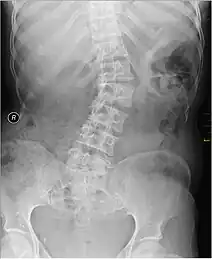

![]() | |

Kyphosis (left) and scoliosis (right) depicting iliocostal contact (a) | |